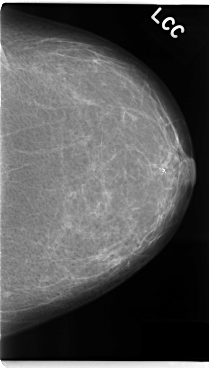

ics_version 1.0 filename C-0131-1 DATE_OF_STUDY 22 9 1995 PATIENT_AGE 48 FILM FILM_TYPE REGULAR DENSITY 1 DATE_DIGITIZED 16 1 1998 DIGITIZER LUMISYS LASER SEQUENCE LEFT_CC LINES 4776 PIXELS_PER_LINE 2712 BITS_PER_PIXEL 12 RESOLUTION 50 NON_OVERLAY LEFT_MLO LINES 4696 PIXELS_PER_LINE 2760 BITS_PER_PIXEL 12 RESOLUTION 50 NON_OVERLAY RIGHT_CC LINES 4736 PIXELS_PER_LINE 2616 BITS_PER_PIXEL 12 RESOLUTION 50 OVERLAY RIGHT_MLO LINES 4704 PIXELS_PER_LINE 2720 BITS_PER_PIXEL 12 RESOLUTION 50 OVERLAY |